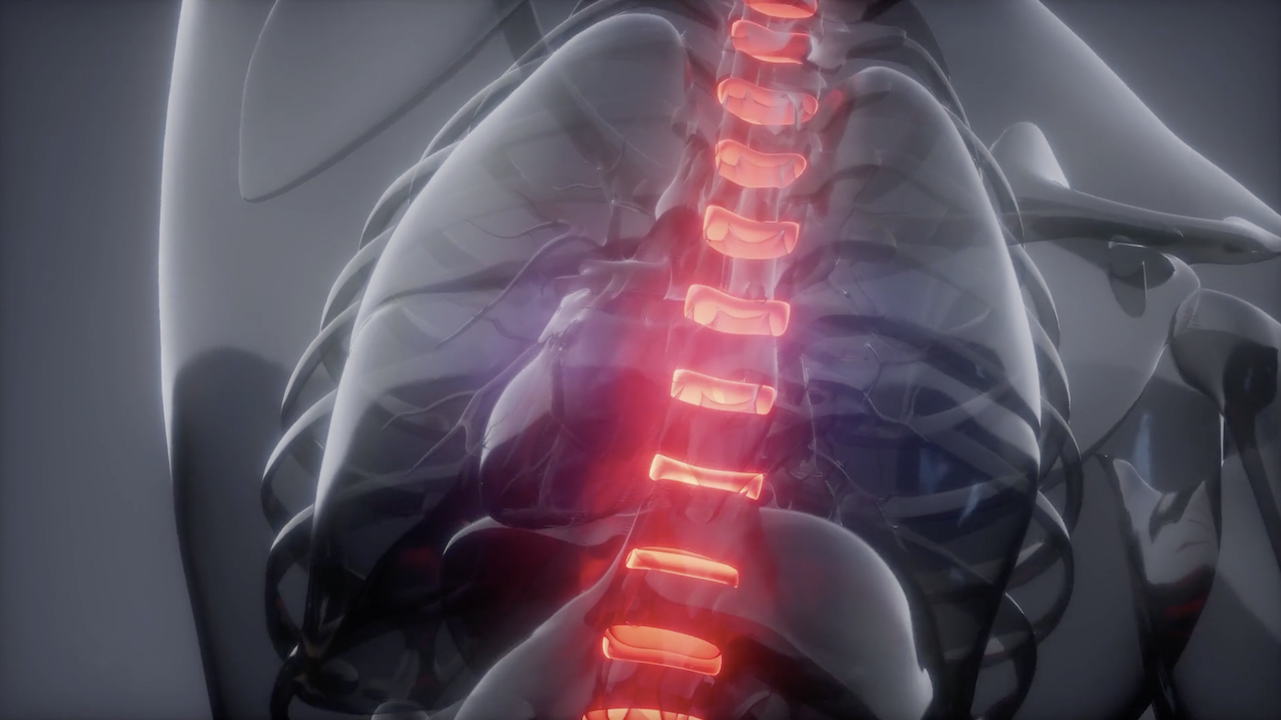

How Spine Tumors Affect The Whole Body and How Ohio State Doctors